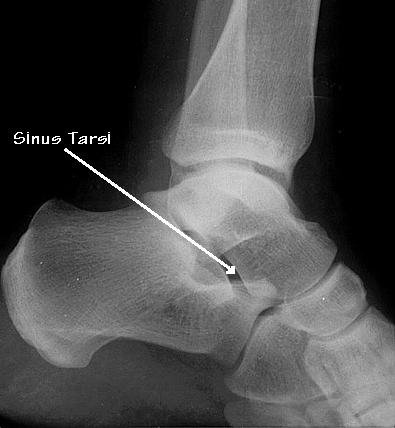

The sinus tarsi is a small 'canal' in the

bone on the outside of the ankle joint. It contains small ligament whose

function is to hold part of the outside aspect of the ankle joint together.